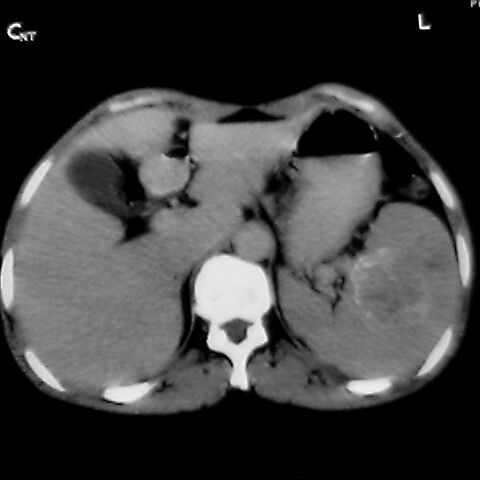

女 48岁 食道癌术前体检发现脾占位。

脾胀内部巨大低密度肿块,边界清或不清,中心坏死,轻度增强,内见散在钙化,结合食道癌病史多考虑:转移癌.

1肝右下叶小囊肿2右肾上极囊肿或错构瘤3脾脏不典型血管瘤可能性大.

脾脏低密度灶伴钙化,增强化明显,中心见液化坏死灶,强化延时明显。考虑血管瘤。转移瘤待排。

右肾见类圆形低密度影.结合病史.脾及右肾转移性ca可能性大